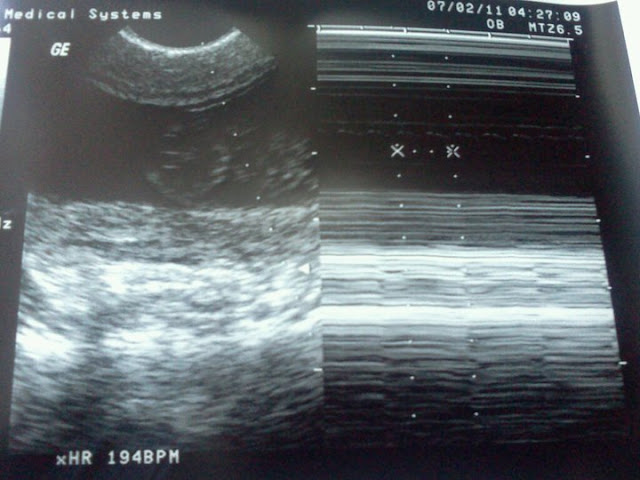

But anyways. She got my appointment going really fast ! Then came the ultrasound time. The Dr. buzzed the nurse and told her to bring in daddy ! So Ben came in the room and we got to see our little munchkin !! It was so amazing. I was in awe ! This little thing was OURS !! Not someone of the TV or some show... but OURS !

She said the baby is healthy every thing is normal! She also told me I could have a 12 pound baby if needed .. my bone structure was built for having babies ! Very good news to hear.